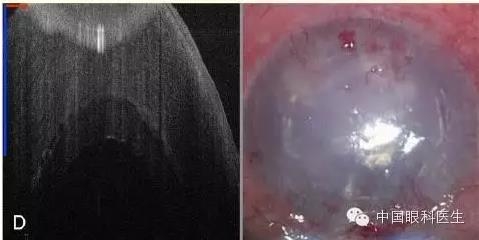

患者男性,28 岁,因左眼视物不清和持续的疼痛至医院就诊,左眼也曾植入人工晶状体,经一系列眼科检查诊断为大泡性角膜病变。患者行 DSAEK 手术时采用的是扫描速度更快的 3D SS-MIOCT 集成显微镜系统(图 2)。

图 2 为 3D SS-MIOCT 集成显微镜系统手术过程;A 为术前;B 为内皮层植入时;C 为填充空气后;D 显示移植内皮层与受体基质层界面间的液体减少;E 移植物与受体贴合良好(图中用红、蓝线段长度表示 1 mm)